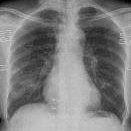

The COVID-19 disease was first discovered in Wuhan, China, and spread quickly worldwide. After the COVID-19 pandemic, many researchers have begun to identify a way to diagnose the COVID-19 using chest X-ray images. The early diagnosis of this disease can significantly impact the treatment process. In this article, we propose a new technique that is faster and more accurate than the other methods reported in the literature. The proposed method uses a combination of DenseNet169 and MobileNet Deep Neural Networks to extract the features of the patient's X-ray images. Using the univariate feature selection algorithm, we refined the features for the most important ones. Then we applied the selected features as input to the LightGBM (Light Gradient Boosting Machine) algorithm for classification. To assess the effectiveness of the proposed method, the ChestX-ray8 dataset, which includes 1125 X-ray images of the patient's chest, was used. The proposed method achieved 98.54% and 91.11% accuracies in the two-class (COVID-19, Healthy) and multi-class (COVID-19, Healthy, Pneumonia) classification problems, respectively. It is worth mentioning that we have used Gradient-weighted Class Activation Mapping (Grad-CAM) for further analysis.

翻译:COVID-19 疾病在中国武汉首次发现,并迅速蔓延到全世界。在COVID-19 流行病后,许多研究人员开始寻找一种方法,利用胸前X光图像诊断COVID-19 。早期诊断该疾病可以大大影响治疗过程。在本篇文章中,我们提出了一种比文献中报告的其他方法更快和更准确的新方法。拟议方法使用DenseNet169 和移动网络深神经网络的组合来提取病人X光图像的特征。在使用单向特征选择算法后,我们改进了最重要的特征。然后,我们将选定特征用作对光GBM(轻度推动机)算法的投入。为评估拟议方法的有效性,使用了ChestX-光8 数据集,其中包括病人胸部的1125 X光图像。拟议方法在两类(COVID-19,健康价值)和多级(COVID-19)中达到了98.54%和91.11%的缩略图。我们分别使用了“高度”的GRAMA-GRA级(C) 分别用于健康等级分析。